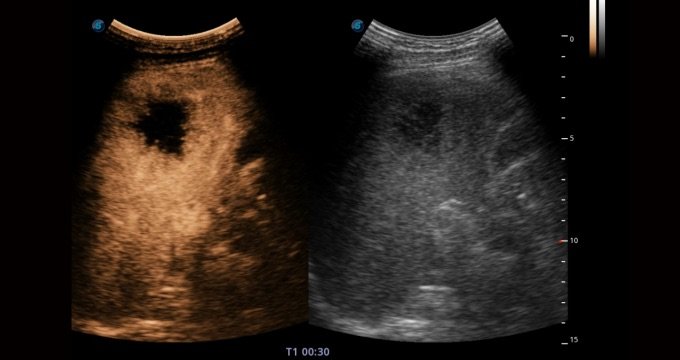

Contrast Imaging

Die Kontrastmittel sorgen für eine starke Signalreflexion, so dass schwer einsehbarer Blutfluss besser dargestellt werden kann. Regelt den Schalldruck und bietet eine vielversprechende Bildqualität bei geringerer Wirkstoffdosis.